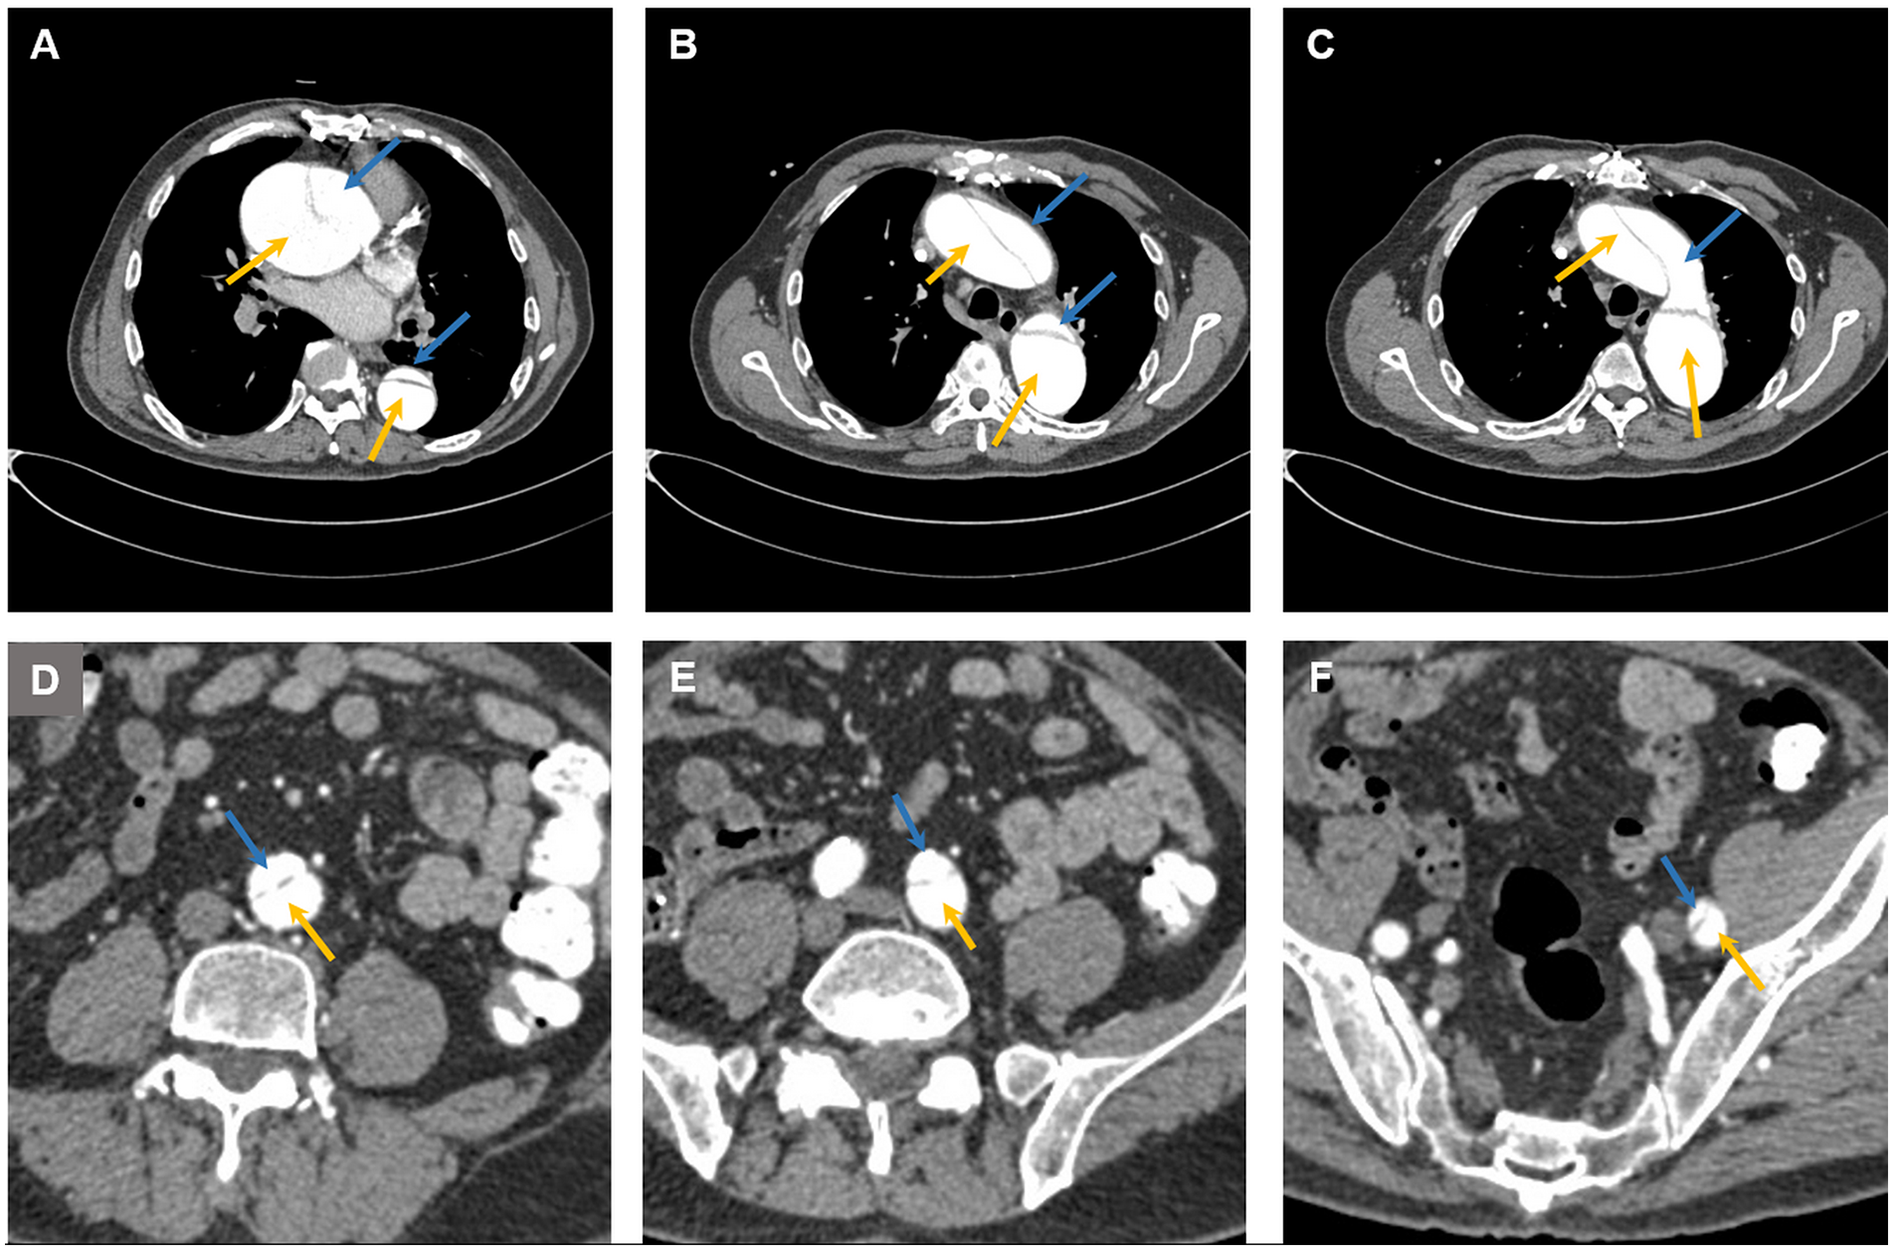

Figure 1

Computed tomography images showing aortic dissection at (A) the aortic root, (B) the ascending aorta, the descending aorta, (C) the aortic arch, (D) the abdominal aorta, (E) the left common iliac artery, and (F) the femoral artery. The blue arrow indicates the false lumen, and the yellow arrow indicates the true lumen.

The patient had a long and complex history of illness (Table 1). The patient had been diagnosed with type A aortic dissection for more than 5 years. Computed tomography (CT) revealed extensive dissection involving the aortic root, the ascending aorta, the aortic arch, the descending aorta, the abdominal aorta, the left common iliac artery, and the femoral artery (Figures 1, 2). The diameter of the ascending aorta remained at 83–89 mm after 2019. Because CT angiography failed to detect the site of the intimal tear and because of the lack of technical capabilities, the patient had not received any repair surgery. When the patient started hemodialysis therapy, low-molecular-weight heparin (LMWH) was not administered because of the concerns about inducing dissection rupture. The anticoagulant-free dialysis pattern frequently caused dialyzer clotting, but could still maintain the patient's normal physiological state.